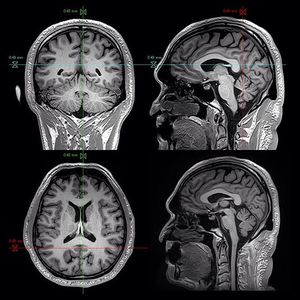

The three-dimensional magnetization-prepared rapid gradient echo (MP-RAGE) sequence is one of the most popular sequences for high-resolution whole brain T1-weighted imaging, with enhanced gray-white matter contrast. The sequence combines the power of magnetization-prepared imaging and rapid 3-D gradient echo acquisition techniques to provide excellent tissue contrasts, high spatial resolution, and full brain coverage in a short scan time. Images acquired with the sequence have been widely used for classifying brain tissues in voxel-based morphometry, detecting pathological changes of the brain, estimating regional brain volume abnormalities associated with brain functions, assessing brain development, and evaluating treatment or therapeutic responses.